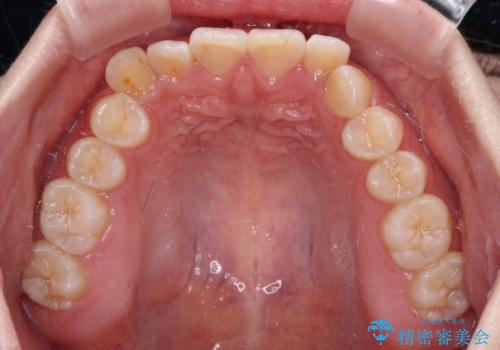

前歯のデコボコを整える インビザラインによる矯正治療

- 上下前歯のデコボコを気にして来院された患者様です。

叢生は軽度であり、ワイヤー矯正でもマウスピース矯正でも対応可能であったので、好きな装置を選んでもらいました。

相談の結果、インビザラインによる矯正治療を行うこととしました。

毎日の装着時間をしっかりと守っていただいたことで、1年程度で無事に治療を終えることができました。